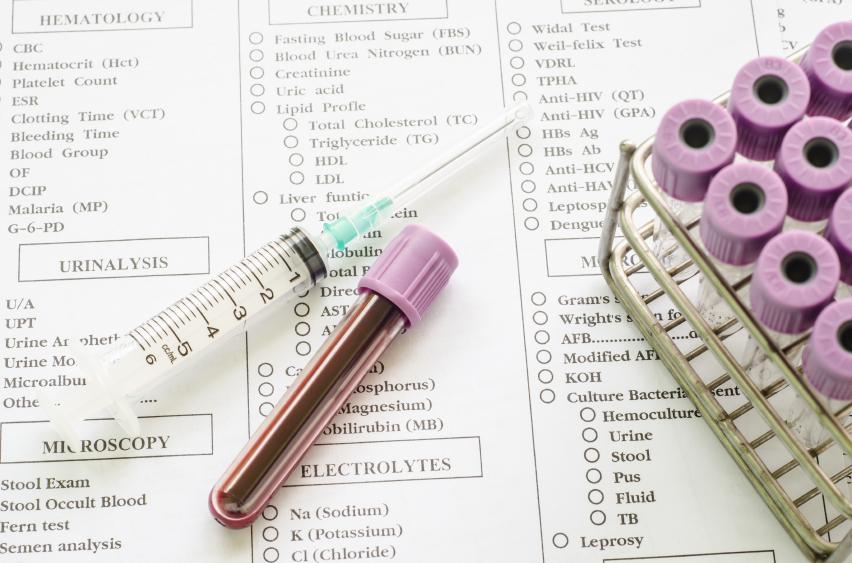

Si estás planeando un embarazo o has quedado recientemente embarazada, es muy importante que acudas cuanto antes al ginecólogo. ¿Por qué es tan necesario visitar a este especialista? Entre otras cosas, porque durante las primeras semanas de gestación el médico te evaluará y realizará un examen de sangre para ver tu salud general y conocer tu inmunidad a las enfermedades peligrosas en el embarazo.

Esta prueba de inmunidad permite determinar, de manera muy clara, si tienes los anticuerpos contra estas enfermedades ya sea porque en el pasado las sufriste, este puede ser el caso de la rubéola o la varicela, o porque has sido vacunada contra ellas. Así conseguirás despejar la gran incógnita y poder determinar si corres el riesgo de sufrir rubéola en el embarazo.